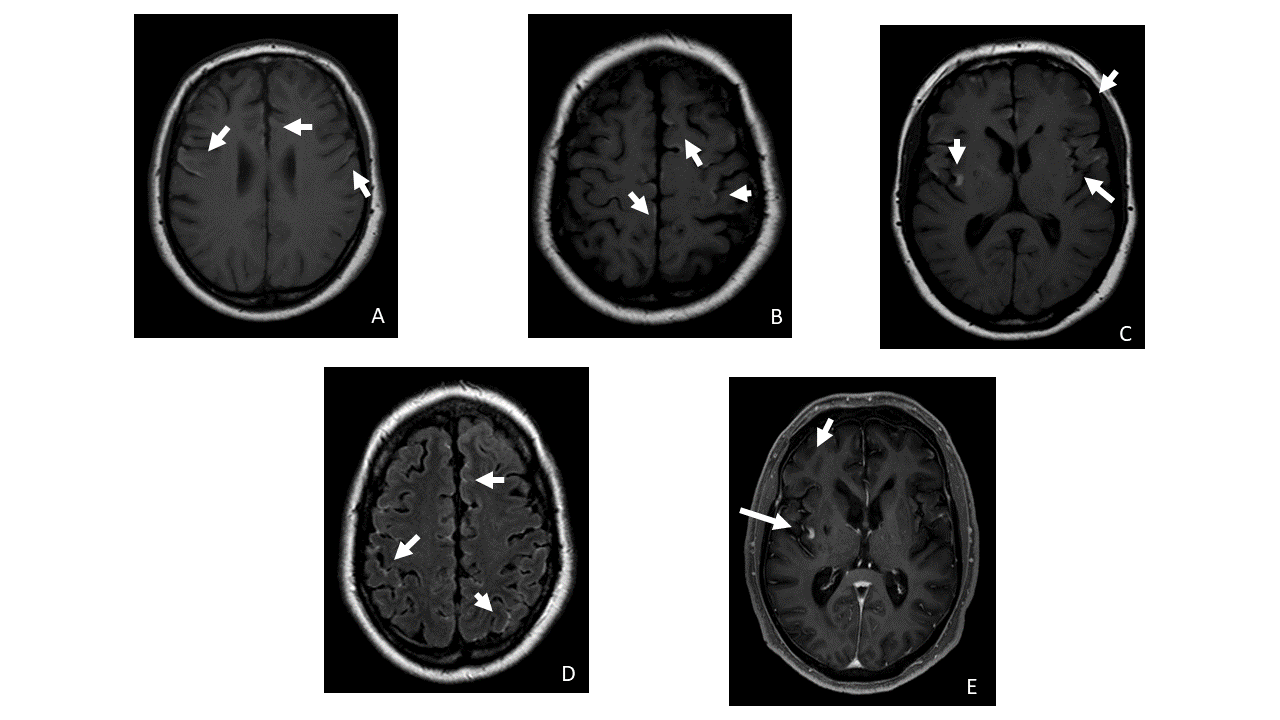

Figuras A, B y C. RM cerebral, secuencias ponderadas en T1, cortes axiales. Figura D-FLAIR axial. Áreas de hiperseñal en la superficie cortical supratentorial de los surcos y circunvoluciones de la convexidad frontal, temporal e insular bilateral

Figura E. T1 tras la administración de contraste, axial. Algunas lesiones presentan captación aunque es de difícil valoración por ser intrínsecamente hiperintensos en T1.

Los hallazgos radiológicos principales son el engrosamiento leptomeníngeo difuso, típicamente hiperintenso en secuencias T1 y FLAIR, hipointenso en T2, y con captación homogénea del contraste.